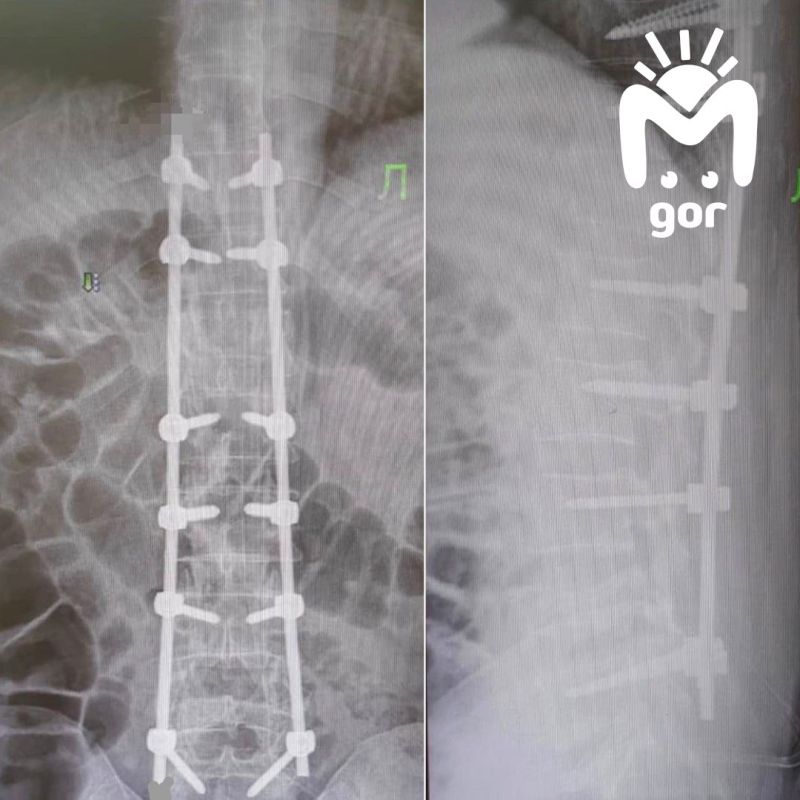

Мужчина попал в нейрохирургию РКБ после того, как серьёзно повредил спину. Позвонки в грудном и поясничном отделах буквально рассыпались, сдавив нервы и спинной мозг. Из-за этого пациент почти перестал чувствовать ноги и не мог передвигаться...

В нейрохирургическом отделении республиканской клинической больницы успешно проведена сложная операция, позволившая вернуть способность к самостоятельному передвижению пациенту с тяжёлой травмой позвоночника.«Мужчина поступил с диагнозом...